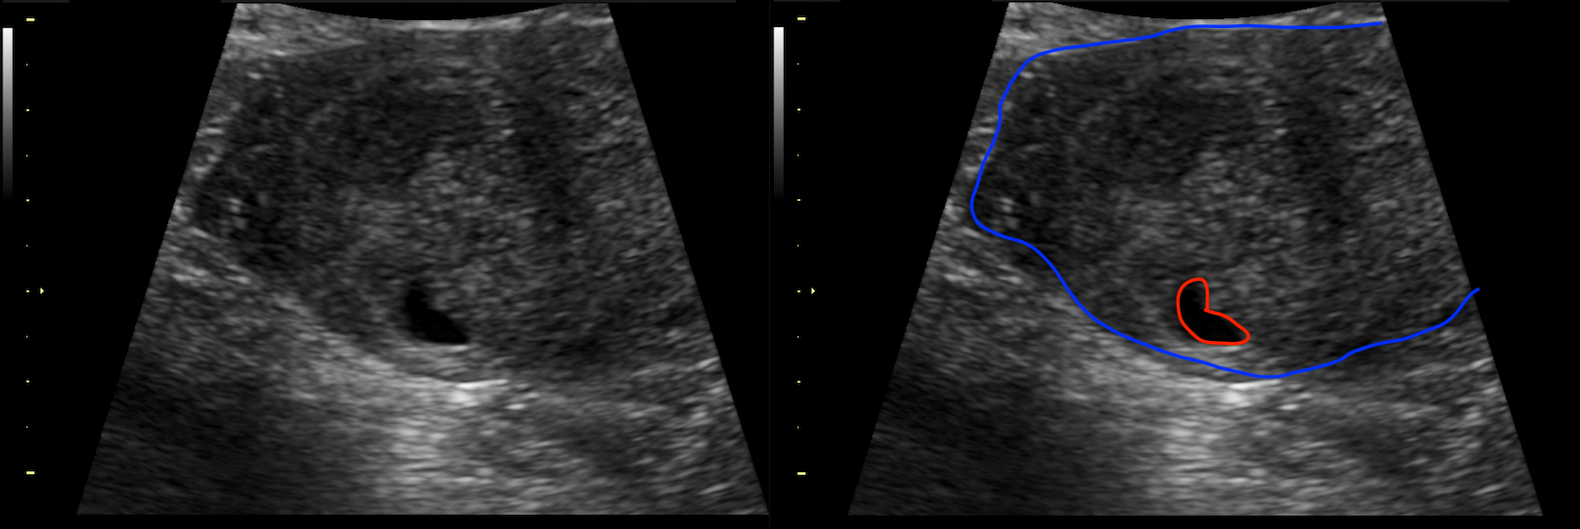

Condition Specific Radiology Heterotopic Pregnancy Stepwards

Condition Specific Radiology Heterotopic Pregnancy Stepwards What Does Radiology Do To Pregnancy it is important for radiology facilities to have procedures to determine the pregnancy status of female patients of reproductive. Generally, the benefits of the. pregnant employees in mri environment. when a pregnant woman with suspected appendicitis is referred for a ct scan, what should a radiologist do to. when physicians request a diagnostic radiology order on. What Does Radiology Do To Pregnancy.

Condition Specific Radiology Heterotopic Pregnancy Stepwards What Does Radiology Do To Pregnancy when physicians request a diagnostic radiology order on pregnant women and have not obtained their. Generally, the benefits of the. Carcinogenesis after exposure to ionizing radiation. pregnant employees in mri environment. when a pregnant woman with suspected appendicitis is referred for a ct scan, what should a radiologist do to. Choosing the most appropriate imaging modality for. What Does Radiology Do To Pregnancy.